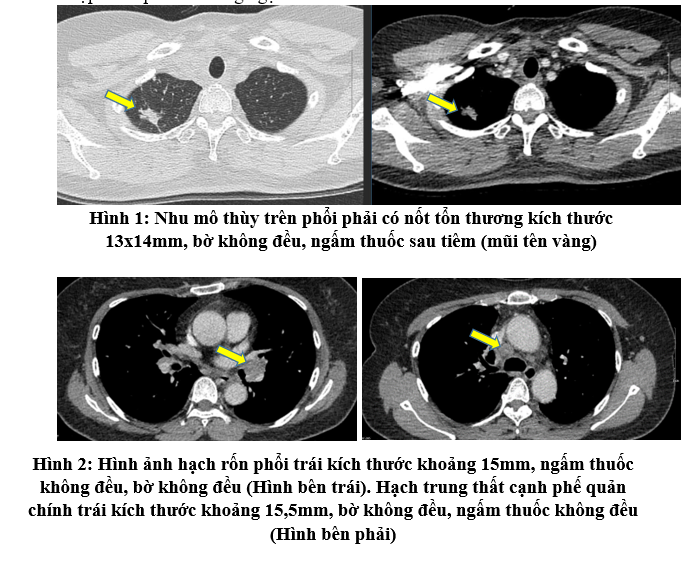

- Chụp cắt lớp vi tính lồng ngực:

Chẩn đoán xác định:

Ung thư biểu mô tuyến thùy trên phổi phải, di căn hạch cT1N3M0 giai đoạn IIIB/ Tăng huyết áp